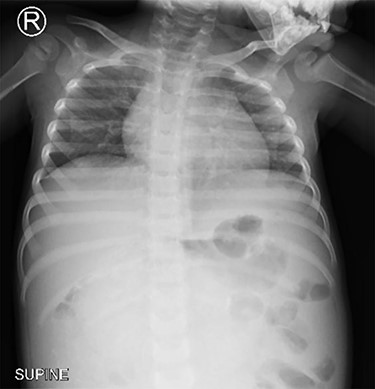

Chest x-ray (Fig. 1) was normal, while abdominal computed tomography (CT) scan showed a huge well-defined heterogenous mass arising from the peritoneal cavity measuring 10.3 cm (AP) × 16.2 cm (T) × 16.7 cm (CC) with central and peripheral calcifications, (Fig. 2). The tumor had pressure effect on the bowels, pancreas and right kidney. The child underwent an elective laparotomy where intraoperatively amber colored ascites was found and a huge left ovarian mass that was free and not adherent to adjacent structures. Left sided salpingo-ophorectomy was done removing the whole mass (Fig. 3) and was sent for histopathology analysis. The uterus, right ovary and fallopian tube were essentially unremarkable. Histopathology of the specimen highlighted a variety of immature and mature tissues derived from the three germ layers (Fig. 4 A–C); whereas a minimal panel of immunohistochemical staining demonstrated strong positivity of the tumor cells for S100 and Neuron specific enolase antibodies (Fig. 4D); thus confirming the diagnosis of immature teratoma, low grade (Grade I), pT2cN0M0. After establishing the diagnosis, the child was reviewed in tumor board by a multidisciplinary team of experts. She recovered well and was discharged on the fourth day postoperatively post discharge; the child attended our pediatric oncology clinic with no any new complaints. She was followed-up with serum chorionic gonadotropin (HCG) and alpha-feto protein (AFP) tests which were within normal during the two monthly visits.